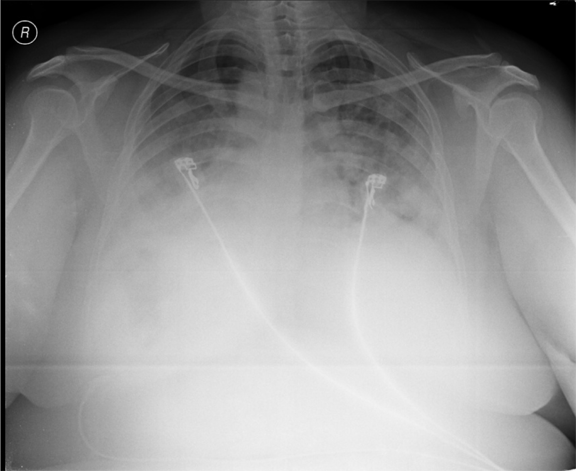

Subsequent investigations revealed corrected reticulocyte count 0.5%, microcytic hypochromic peripheral blood smear, low serum iron (36 μg/dL), low transferrin saturation (28%), normal Ferritin (140.2 ng/mL), normal total iron binding capacity (415 μg/dL) and normal serum vitamin B12 and folic acid levels. Her stool was negative for occult blood or parasites. Her serum creatinine was 0.8 mg/dL, blood urea was 36 mg/dL and urine microscopy was normal (no protein or red blood cells). The liver function tests and coagulation profile were within normal limits. Her retroviral status (HIV I and II by ELISA), hepatitis B surface antigen and hepatitis C antibody were negative. She received one pint blood transfusion in the ICU. Her chest X-ray (Figure 1) which was done in the ICU showed bilateral reticular infiltrates. Computed tomography (CT) scan of thorax was subsequently done which showed bilateral extensive ground glass opacities with interstitial thickening and nodules. (Figure 2) A provisional diagnosis of acute interstitial pneumonia/diffuse alveolar hemorrhage was made and she was started on broad spectrum antibiotics with high dose pulse steroids (Inj methylprednisolone 500 mg i.v. daily in divided doses for 3 days). Within 3 days she improved significantly and was weaned off the non invasive ventilator support. Later the steroids were tapered to oral prednisolone at 0.75 mg/kg body weight. Subsequently fibre optic bronchoscopy was done under local anesthesia with conscious sedation. Sequential broncho alveolar lavage (BAL) was done from right middle lobe, it showed increasing hemorrhagic returns of BAL aliquots and BAL counts showed 60% hemosiderophages, (Figure 3) confirming the diagnosis of diffuse alveolar hemorrhage. BAL was negative for gram stain and culture showing no evidence bacterial pathogens, acid fast bacilli, fungal organism, Fluorescent antibody stain for Pneumocystis jeroveci and cytology for cancer cells. Transbronchial lung biopsy was done from right middle and lower lobes. It showed interstitial fibrosis, hemosiderin laden macrophages in alveolar spaces and interstitium with positive Perl’s stain. (Figure 4) There was no evidence of vasculitis (capillaritis), granulomas, organising pneumonia and malignancy in the biopsy specimen. Her serum Rheumatoid factor (RF), antinuclear antibody (ANA), Double stranded Deoxyribonucleic acid (DsDNA), antiphospholipid antibody(APLA), Anti Glomerular Basement Membrane antibody (anti GBM) and anti U1 RNP were negative. Serum Complements (C3, C4 and Total Complement) and Antineutrophilic Cytoplasmic antibodies(c and p ANCA) were in normal range. After one week of treatment with steroids, she improved and there was no further drop in hemoglobin. At this time spirometry was done and it was normal. Her chest X-ray and CT thorax repeated after one month showed complete clearing of the shadows. (Figure 5)

Figure 5: Post treatment computed tomography chest showing significant resolution.